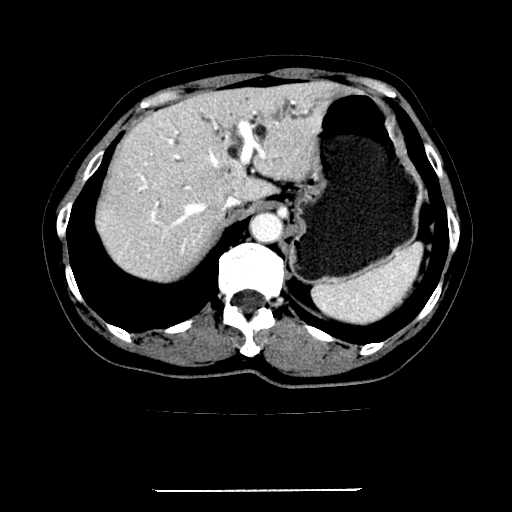

标题: CT22301:女,67岁,上腹部疼痛一周伴皮肤黄染,无发热。 [打印本页]

女,67岁,上腹部疼痛一周伴皮肤黄染,无发热。

左叶肝内胆管结石,并远端肝内胆管扩张。

考虑:肝内胆管结石继发肝内胆管扩张,右肾旋转不良。

肝内外胆管结石并肝内胆管扩张。

建议薄层观察,除外肝门部胆管细胞癌

考虑肝胆管癌;胰头占位?【形态失常,体积增大】

1、肝门高密度影下层面和胰头层面可见轻度胆管扩张,而静脉和延迟期均未见扫描完胰头,不能完全排除胰头占位。2、肝门部高密度影,考虑钙化或结石。

考虑肝门胆管癌伴门脉左支受侵包埋,建议mrcp进一步检查。